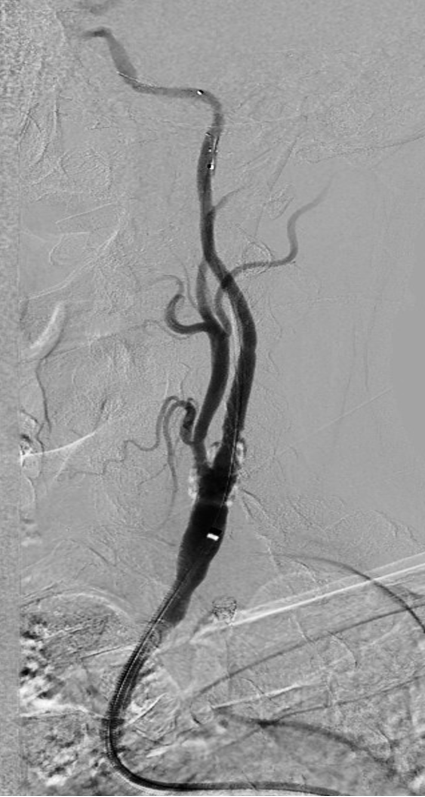

CASE 3:74岁女性,左侧颈动脉重度钙化狭窄,IVL治疗后管腔获得理想,支架置入后残余狭窄低。

左侧颈动脉

重度钙化狭窄

IVL后即刻管腔

获得理想

支架后

残余狭窄低